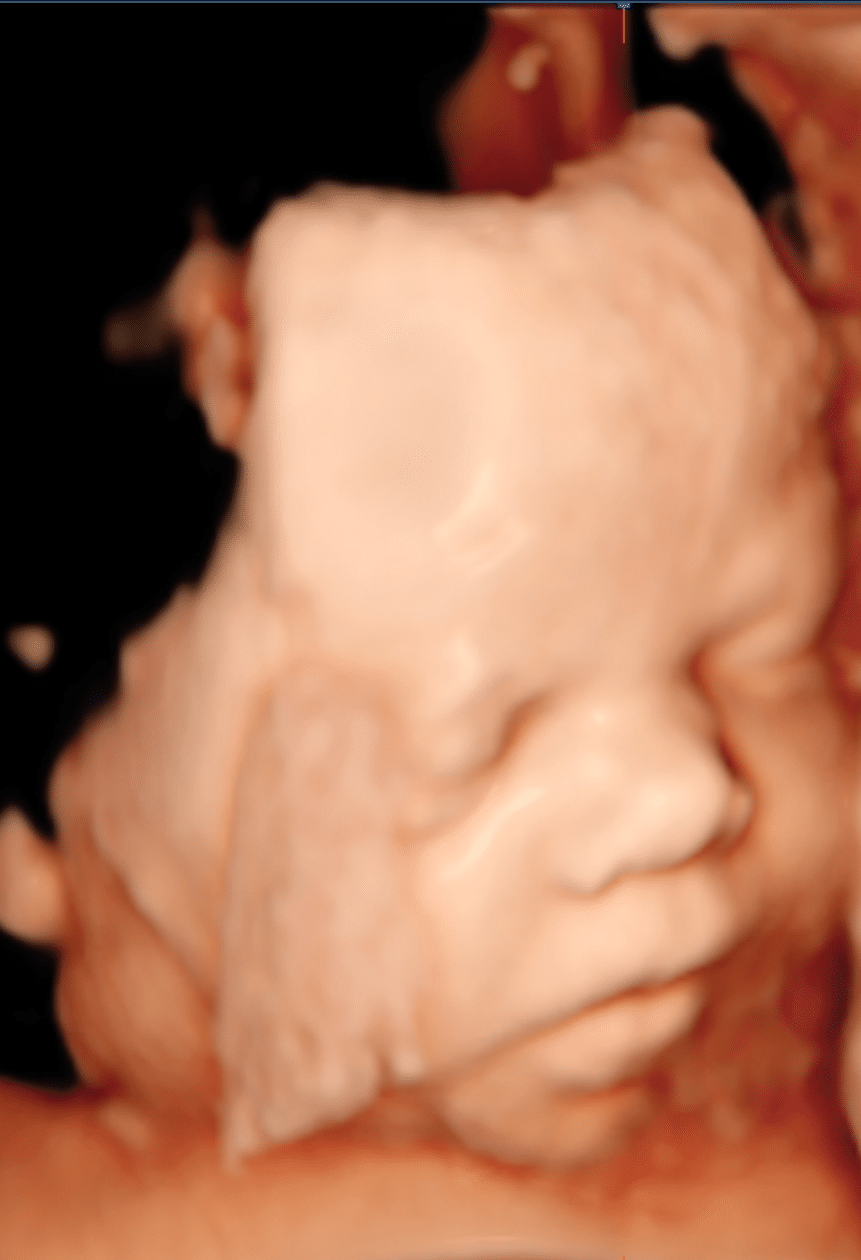

Babamozi (3D/4D szülészeti ultrahangvizsgálat)

A babamozi során modern 3D/4D ultrahang-technológiát használunk, amely lehetővé teszi, hogy a magzat arcát, mozdulatait, ásítását, mosolyát vagy akár az ujjacskái mozgatását is megfigyelhessük. Az eljárás nem orvosi vizsgálat, hanem elsősorban egy vizuális élmény, mely érzelmi tartalommal  egészíti ki a terhesgondozási vizsgálatokat. Ilyenkor nincs diagnosztika, vagy egészségügyi értékelés – a fókusz kizárólag azon van, hogy a szülők közelebb kerüljenek a babához, és átélhessék az első „találkozást”.

A vizsgálat elején minden esetben ellenőrizzük a baba életjelenségeit, elsősorban a magzati szívritmust, ezt követően pedig megkeressük azokat az optimális testhelyzeteket, amelyek a lehető legszebb és legélesebb felvételek elkészítését teszik lehetővé. A jó képminőség feltétele, hogy a baba arca és teste előtt elegendő magzatvíz álljon rendelkezésre.

A magzatok rendkívül változatos pozíciókban helyezkedhetnek el, hosszirányban, keresztben, átlósan, arccal lefelé. Gyakran előfordul, hogy a baba kezei vagy lábai az arca előtt vannak, körülötte úszik a köldökzsinór, illetve a méhlepényhez simul, amelyhez előszeretettel bújik. Emiatt előre nem kiszámítható, hogy egy adott pillanatban mit és mennyi ideig tudunk megfigyelni.